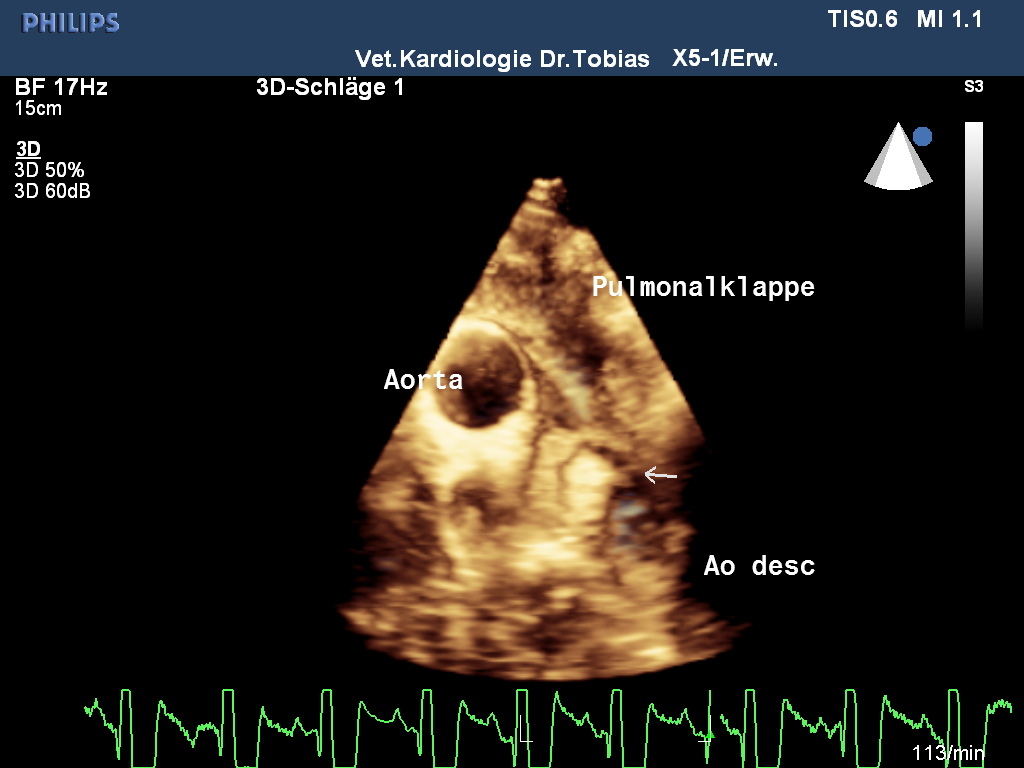

Neben der Auskultation und dem Röntgen stehen dem Veterinärkardiologen die gleichen Untersuchungsmethoden zur Verfügung, wie sie auch in der Humanmedizin Anwendung finden: das Elektrokardiogramm erlaubt eine Rhythmus und Frequenzanalyse, die Blutdruckmessung ist ungleich schwieriger als in der Humanmedizin und spielt bei Katzen eine größere Rolle als beim Hund, das Fundament der Kardiologie ist die Herzultraschalluntersuchung, die den Sitz und die Charakterisierung der Krankheit erlaubt sowie eine Schweregradbestimmung. Zur anatomischen Darstellung werden ein- und zweidimensionale Methoden genutzt, auch 3D- und 4D–Methoden sind in spezialisierten Einrichtungen zu finden. Die Blutflussdarstellung erfolgt mit verschiedenen Dopplermethoden, die viele Hundebesitzerinnen auch aus Schwangerschaftsuntersuchungen kennen. Neuere Methoden zur Herzmuskeluntersuchung sind die Speckle Tracking- und Gewebedopplermethoden.

Rike wurde einer modernen Echokardiographieuntersuchung nach nationalem und internationalem Standard unterzogen und zusätzlich eine 3D/4D-Bildbetrachtung vorgenommen und ihre Herzmuskelleistung via Speckle Tracking untersucht. Die Untersuchung bestätigte eine offene Verbindung zwischen Aorta und Pulmonalrterie, die sich bei der Geburt hätte schließen müssen. Durch die Volumen und Drucküberladung kommt es zu einer Linksherzbelastung, die zu einer deutlichen Vergrößerung der linken Kammer geführt hat. Infolge der Kammervergrößerung wird die linke Vorkammer-Kammerklappe undicht und zunehmend Blut in Richtung Lunge zurücklassen, was das Stauungsrisiko weiter steigert. Typischerweise erhöht sich wie auch bei Rike der Aortendruck, ohne dass anatomische Anzeichen einer Stenose festzustellen wären. In der Pulmonalarterie ist im Farbdoppler ein chaotisch-turbulentes Signal zu sehen, während die Ductusampulle laminar bleibt. Im EKG zeigten sich bereits verlängerte Überleitungszeiten im Kammerkomplex QRS und Senkung des ST-Segmentes, als Zeichen einer Hypoxie des Herzmuskels.